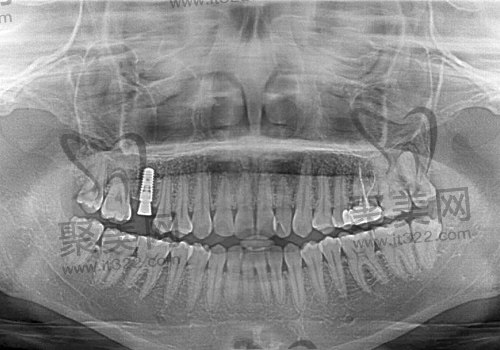

iti种植体的材质以四级纯钛材质制成,也是受到更多人推荐的一款种植体,它的特点就是与牙骨骨结合的地方属于中空柱状结构,并在种植体上有横向的孔洞,这样的设计有利于口腔内骨组织的长入,并且表面也是经过特殊处理,致使口腔内有益物质附着在种植体表面,附近伤口的快速愈合,同时让骨结合与种植体的时间也是大大缩减到2-3个月呢,软骨组织的感染几率也是降低了不少,是被国内外公认为稳定性非常好的一款种植系统,其特点就是成活几率高、治疗时间短、恢复、快及使用时间长著称。

首先瑞士iti种植体拥有三个型号,包含:iti非亲水型种植体(常规标准版)、iti亲水型种植体、iti瑞锆钛锆合金亲水型种植体,它们在价格上都大不同。

1.iti非亲水型种植体:10800元起/颗

非亲水型种植体表面经过SLA喷砂酸蚀处理,其与咱们口腔内的相容性是非常不错的,并且种植周边炎症也是大大降低,不会产生排斥反应。

2.iti亲水种植体:15800元起/颗

这个型号在初期拥有较为不错的稳定性,而且月牙槽骨之间的愈合时间也是大大缩短了不少,植体表面也是经过特殊技术处理。具备了良好的诱导能力,也能够促进牙骨量的一个恢复,能够有效阻止病毒的入侵,然然几率更是极低。

3.iti瑞锆钛锆合金亲水型种植体:23800元起/颗

此款种植体是寝室u行种植体的升级版,它不仅拥有亲水型的优点,而且其在强度上也得到了大幅度的提升,也满足了一些人群喜欢吃硬性食物的需求。